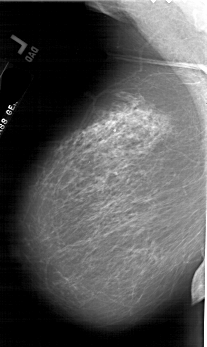

A_1773_1.LEFT_CC

LEFT_CC LINES 6196 PIXELS_PER_LINE 3931 BITS_PER_PIXEL 12 RESOLUTION 43.5 NON_OVERLAY